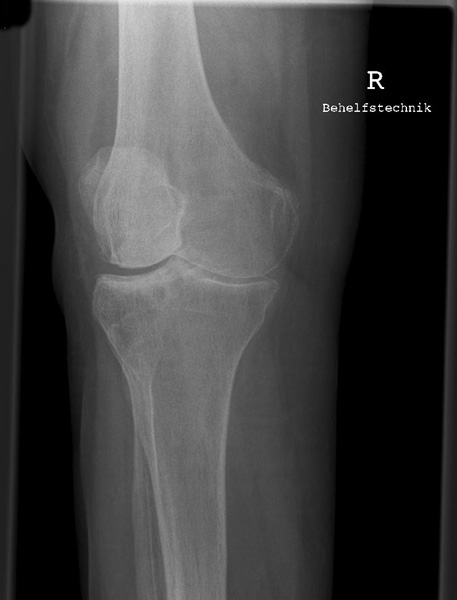

Knie a.p.

121_3.jpg

Fehler

Die Patella ragt über die laterale Begrenzung des distalen Femur hinaus, gleichzeitig projiziert sich das ganze Fibularköpfchen in dem Tibiakopf. Überdies wird dann das Tuberculum intercondylare mediale von der medialen Gelenkrolle des Femus verschattet. Bei dieser Fehleinstellung lassen sich z.B. posttraumatische Verkalkungen, die medial am inneren Gelenkknorren des Oberschenkels liegen (sog. Stieda-Pellegrinische Schatten), nicht mehr erkannt werden.

Abhilfe

Der nach außen schauende Fuß muss leicht, also nicht zu stark, nach innen gedreht werden, Großzehenwärts.